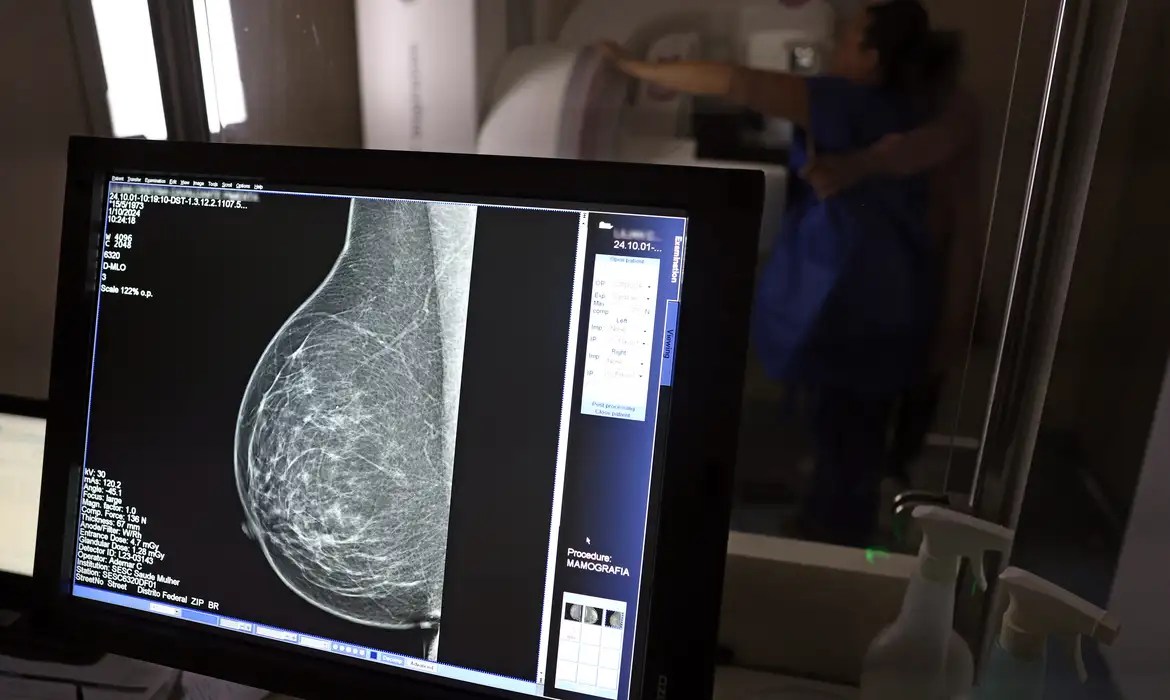

<p>O <a href="https://www.portalitapipoca.com.br/tag/ministerio-da-saude" target="_blank" data-type="link" data-id="https://www.portalitapipoca.com.br/tag/ministerio-da-saude" rel="noreferrer noopener">Ministério da Saúde</a> anunciou, nesta terça-feira (23), a ampliação do acesso à mamografia pelo Sistema Único de Saúde (SUS). A partir de agora, mulheres de 40 a 49 anos poderão realizar o exame mesmo sem sinais ou sintomas de câncer de mama. A pasta informou que essa faixa etária concentra 23% dos casos da doença, e que a detecção precoce aumenta significativamente as chances de cura.</p>

<p>Até então, a recomendação era que a mamografia fosse realizada apenas a partir dos 50 anos. Com a mudança, o exame para mulheres de 40 a 49 anos poderá ser solicitado sob demanda, em decisão conjunta entre paciente e profissional de saúde. “A paciente deve ser orientada sobre os benefícios e desvantagens de fazer o rastreamento”, destacou o ministério em nota.</p>

<p>Segundo dados oficiais, em 2024, cerca de 30% das mamografias realizadas no SUS foram feitas em mulheres com menos de 50 anos — o que corresponde a mais de 1 milhão de exames.</p>

<p>O ministério também ampliou a faixa etária para o rastreamento ativo, quando a mamografia preventiva é oferecida a cada dois anos. Antes restrito a mulheres de até 69 anos, agora o limite passa a ser 74 anos. A decisão acompanha práticas internacionais e considera que quase 60% dos casos de câncer de mama estão concentrados entre 50 e 74 anos.</p>

<p>Somente em 2024, o SUS realizou aproximadamente 4 milhões de mamografias para rastreamento e 376,7 mil exames diagnósticos.</p>